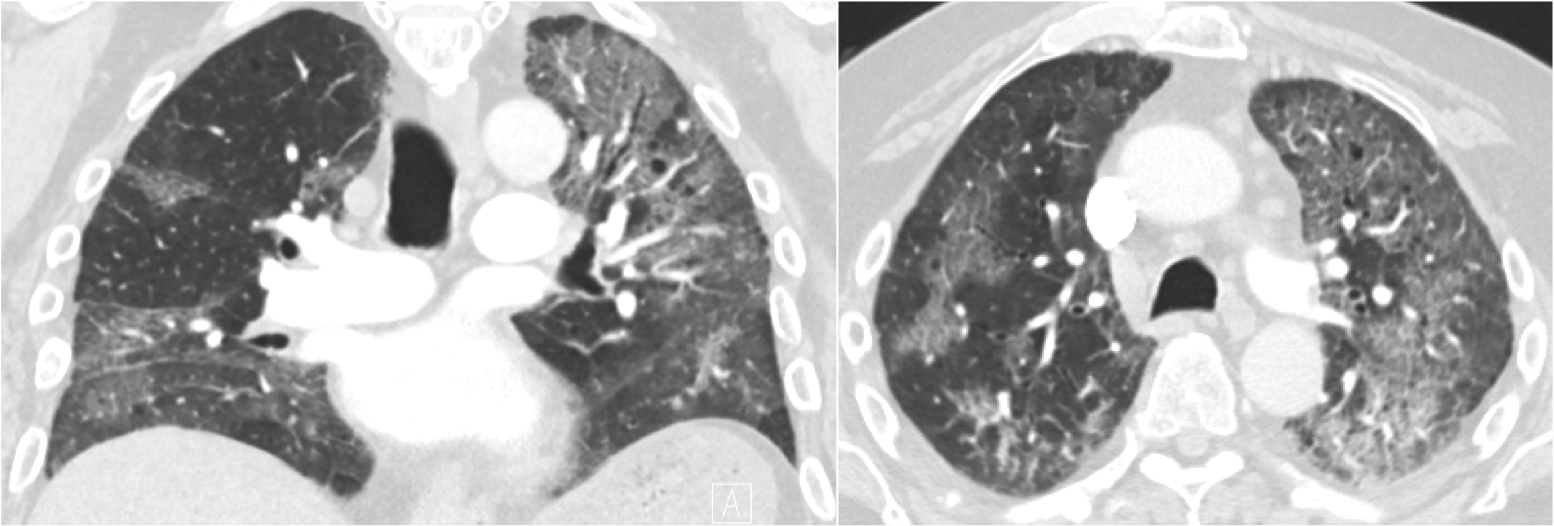

Figure 2Case 2: Coronal and axial computed tomography scans of the chest after the administration of contrast demonstrate bilateral ground-glass opacities with associated septal thickening, small pleural effusions, and the absence of hilar adenopathy.

A 76-year-old male with a history of prostate cancer treated with radical prostatectomy presented years later with dysphagia, hoarseness, facial droop, and tongue deviation. Brain MRI revealed metastatic disease with a large skull base mass extending from the left occipital bone to the left hypoglossal canal and jugular foramen. The mass also involved cervical vertebrae 1. Given his neurologic symptoms, the patient was started on 8 mg dexamethasone twice daily and underwent evaluation by radiation oncology for palliative radiation. He was also started on bicalutamide and leuprolide for metastatic prostate cancer. At the time of discharge, he was tapered from 8 mg dexamethasone twice daily to 4 mg dexamethasone twice daily and received follow-up in the outpatient setting with radiation therapy for the metastases in the base of his skull. During this time, he was maintained on dexamethasone 4 mg twice daily (>50 mg prednisone equivalent/day) for a total of 34 days until radiation therapy was complete. While tapering dexamethasone at a daily dose of 2 mg, the patient experienced sudden onset lethargy and weakness. On arrival to the emergency department, he was found to be in acute hypoxic respiratory failure and was admitted to the medical intensive care unit for workup. A CT scan of the chest revealed diffuse bilateral ground-glass opacities and multiple subsegmental pulmonary emboli (Figure 2). He was initially treated with therapeutic anticoagulation; however, given the lack of improvement in his respiratory status, he underwent bronchoscopy with bronchoalveolar lavage (BAL). The BAL fluid tested positive for Pneumocystis jirovecii. The patient was treated with high-dose prednisone and pentamidine and was discharged with improvement in his respiratory status.

In patients without HIV infection presenting with respiratory complaints, there is a longer time to diagnosis of PCP and this is an independent risk factor for death.13 Patients with solid tumors are at risk for common causes of pulmonary processes, but Pneumocystis jirovecii should remain on a provider’s differential diagnosis in the appropriate situation. When considering PCP as a differential diagnosis, a thorough review of the patient’s clinical course, medications, and imaging should be done. Imaging can often be nonspecific with perihilar and mid-to-apical predominant ground-glass opacities on radiography and CT. When determining whether a pulmonary infiltrate is PCP versus radiation pneumonitis, it is important to recall that radiation pneumonitis is a more geographic finding with confluent ground-glass opacities that are confined to the path of radiation. For PCP, pneumatoceles without pleural effusion and lymphadenopathy can be seen in 30% of cases.21